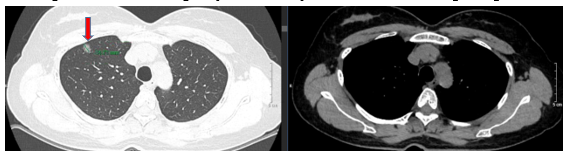

- Chụp cắt lớp vi tính lồng ngực (trước mổ), kết quả cho thấy: Nhu mô thùy trên phổi phải có nốt bán đặc bờ không đều đường kính 10mm (có tính chất ác tính), nốt kính mờ đường kính 7mm. Không thấy hạch to hay khối choán chỗ trong trung thất.

Hình 1: Hình ảnh cắt lớp vi tính lồng ngực trước mổ có nhu mô thùy trên phổi phải có nốt bán đặc bờ không đều đường kính 10mm (mũi tên đỏ)